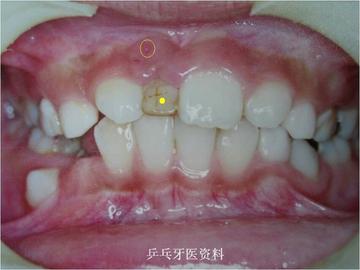

下面这两张图片显示一10岁患儿右上乳牙(黄点标记)根尖反复发炎导致对应门牙(红点标记)不能萌出。左边门牙正常萌出。

口内照片示:右上乳牙牙根发炎(黄圈示瘘管)对应恒牙不能萌出